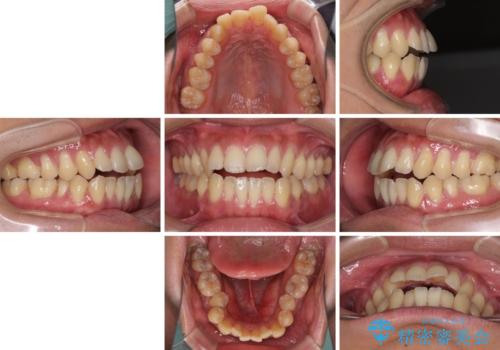

隙間が空いて突出した前歯を治したい ワイヤー装置による抜歯矯正

- 上下前歯の隙間と口元の出っ張った感じを気にして来院された患者様です。

上下の隙間は舌突出癖によるもので、またその癖により前歯が前方に出ている状態でした。

口元の出っ張りを改善するため、上下左右第一小臼歯4本を抜去し、ワイヤー装置にて矯正治療を行うこととしました。

舌の突出癖を改善するためのトレーニングを指導していましたが、なかなか改善することができず、ワイヤー装置を外してからも上下前歯に隙間ができやすい状況でした。